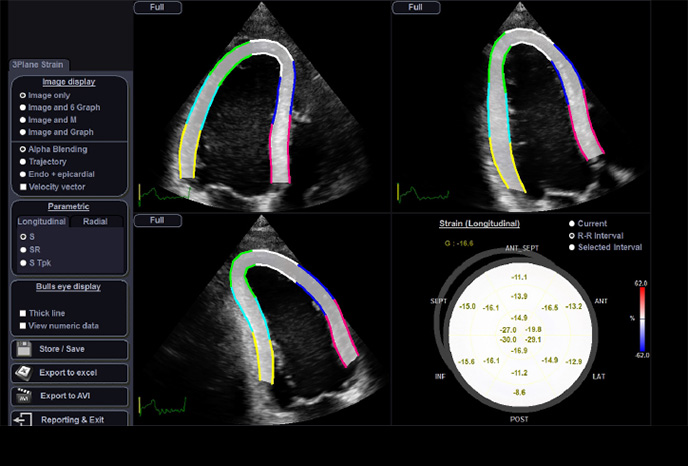

Strain+

Strain + je kvantitativní nástroj pro měření celkového a segmentového pohybu stěny levé komory (LV). Ve Strain + se na obrazovce zobrazují tři standardní pohledy levé komory a Bull's Eye pro snadné a rychlé vyhodnocení funkce LV.